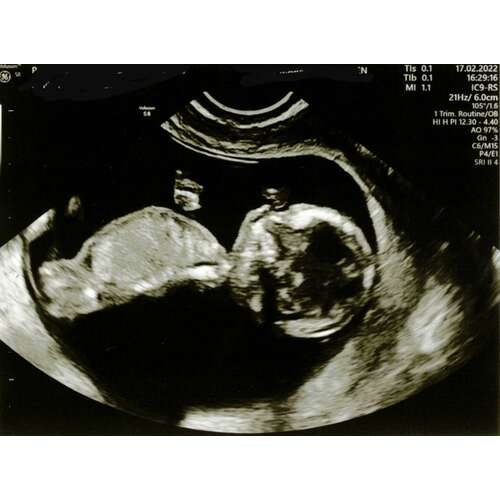

Hier ben ik 11+6, denk net iets te vroeg om het te kunnen zien. Wellicht dat iemand wel al wat kan zien. Ben zo benieuwd ☺️

Ja op het randje niet heel betrouwbaar nog. Had je een tweede foto!

Hoi nubster🙂 ik heb nog 2 andere echo foto’s. Misschien zijn deze iets duidelijker? Baby’tje ligt wel ietsjes naar z’n linkerzijde

En de 2e foto